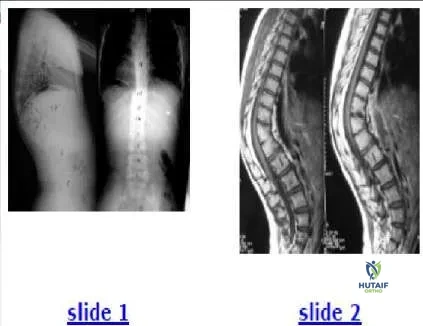

An 8-year-old girl with no history of fever, illness, or weakness presents with an increasing spinal deformity. She was born in Asia. The patient is neurologically normal. Based on radiographs (Slide 1) and magnetic resonance images (Slide 2), the most likely diagnosis is:

Orthopedic Prometric Exam Chapter 3 Image This patient has congenital kyphosis. The relative disk destruction with vertebral preservation argues against tuberculosis. The anterior bony wedging is atypical for remote bacterial infection. Anterior fusion is not seen in patients with Scheuermann kyphosis (rarely after maturity) or in patients with compression fractures.